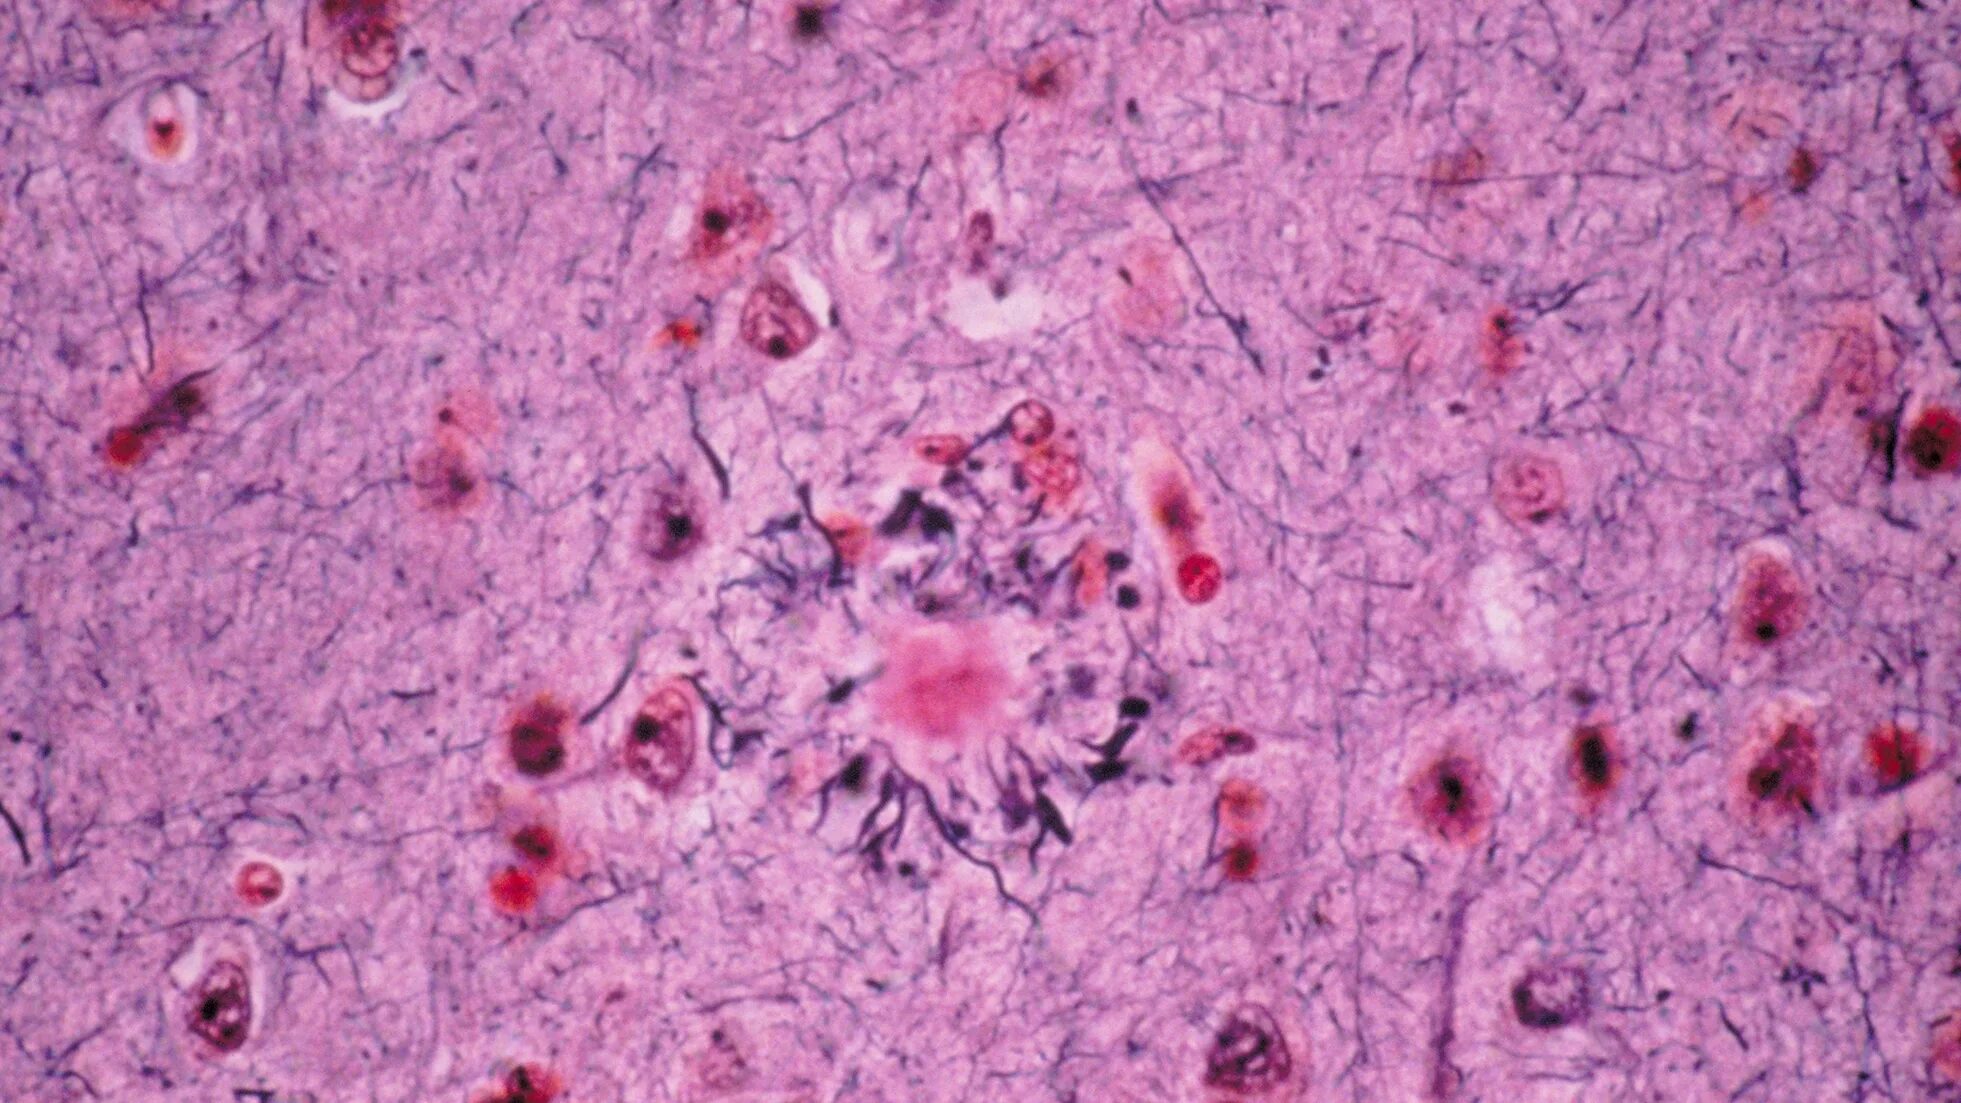

Гистологические заболевания